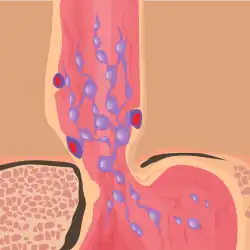

Normal portal pressure is approximately 9 mmHg compared to an inferior vena cava pressure of 2–6 mmHg. This creates a normal pressure gradient of 3–7 mmHg. If the portal pressure rises above 12 mmHg, this gradient rises to 7–10 mmHg.[5] A gradient greater than 5 mmHg is considered portal hypertension. At gradients greater than 10 mmHg, blood flowing through the hepatic portal system is redirected from the liver into areas with lower venous pressures. This means that collateral circulation develops in the lower esophagus, abdominal wall, stomach, and rectum. The small blood vessels in these areas become distended, becoming more thin-walled, and appear as varicosities.

In situations where portal pressures increase, such as with cirrhosis, there is dilation of veins in the anastomosis, leading to esophageal varices.[3] Splenic vein thrombosis is a rare condition that causes esophageal varices without a raised portal pressure. Splenectomy can cure the variceal bleeding due to splenic vein thrombosis.

Varices can also form in other areas of the body, including the stomach (gastric varices), duodenum (duodenal varices), and rectum (rectal varices). Treatment of these types of varices may differ. In some cases, schistosomiasis also leads to esophageal varices.